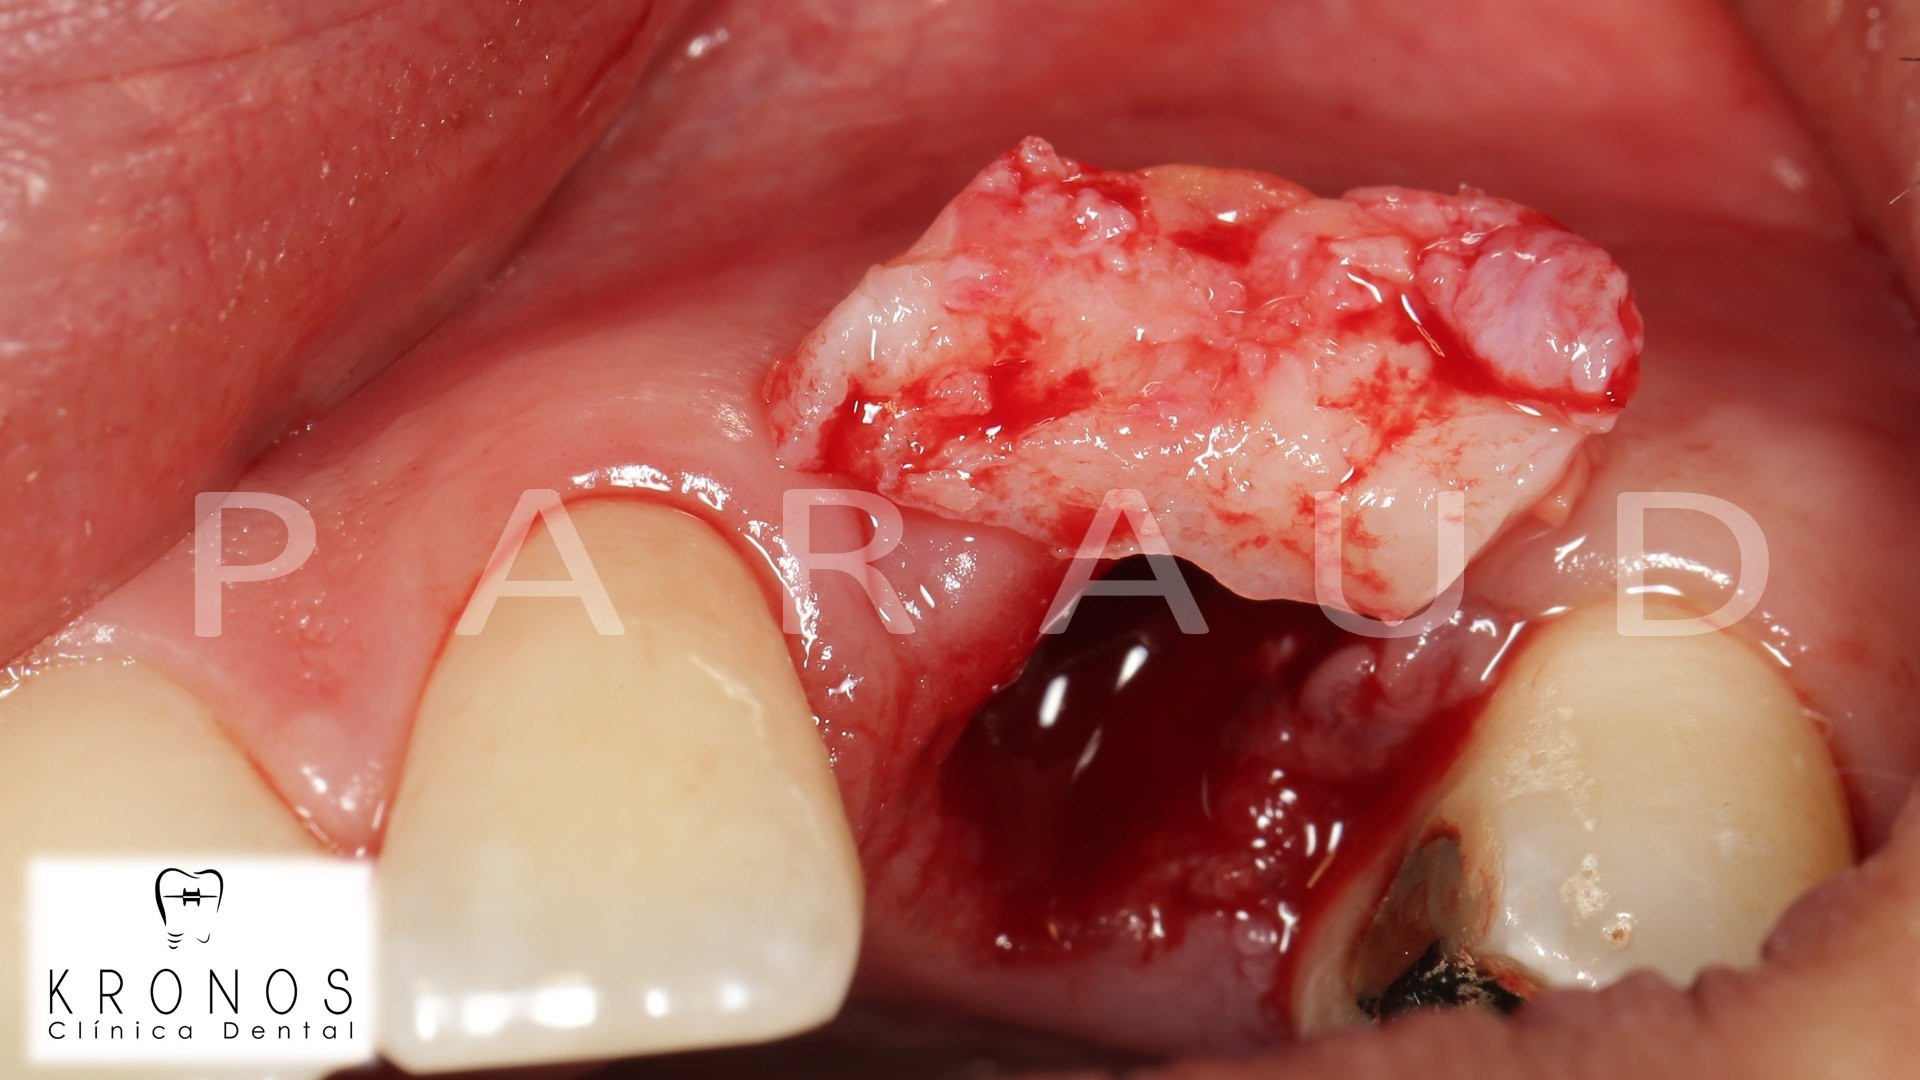

Clinical case: AnyRidge immediate loading

- Courtesy of Dr. Andres Paraud Freixas, Chile -

AnyRidge, ISQ value, initial stability, immediate loading, KnifeThread, maxillary anterior, Mega ISQ, Dr. Andres Paraud Freixas

AnyRidge implant system, Mega ISQ, Digital prosthesis